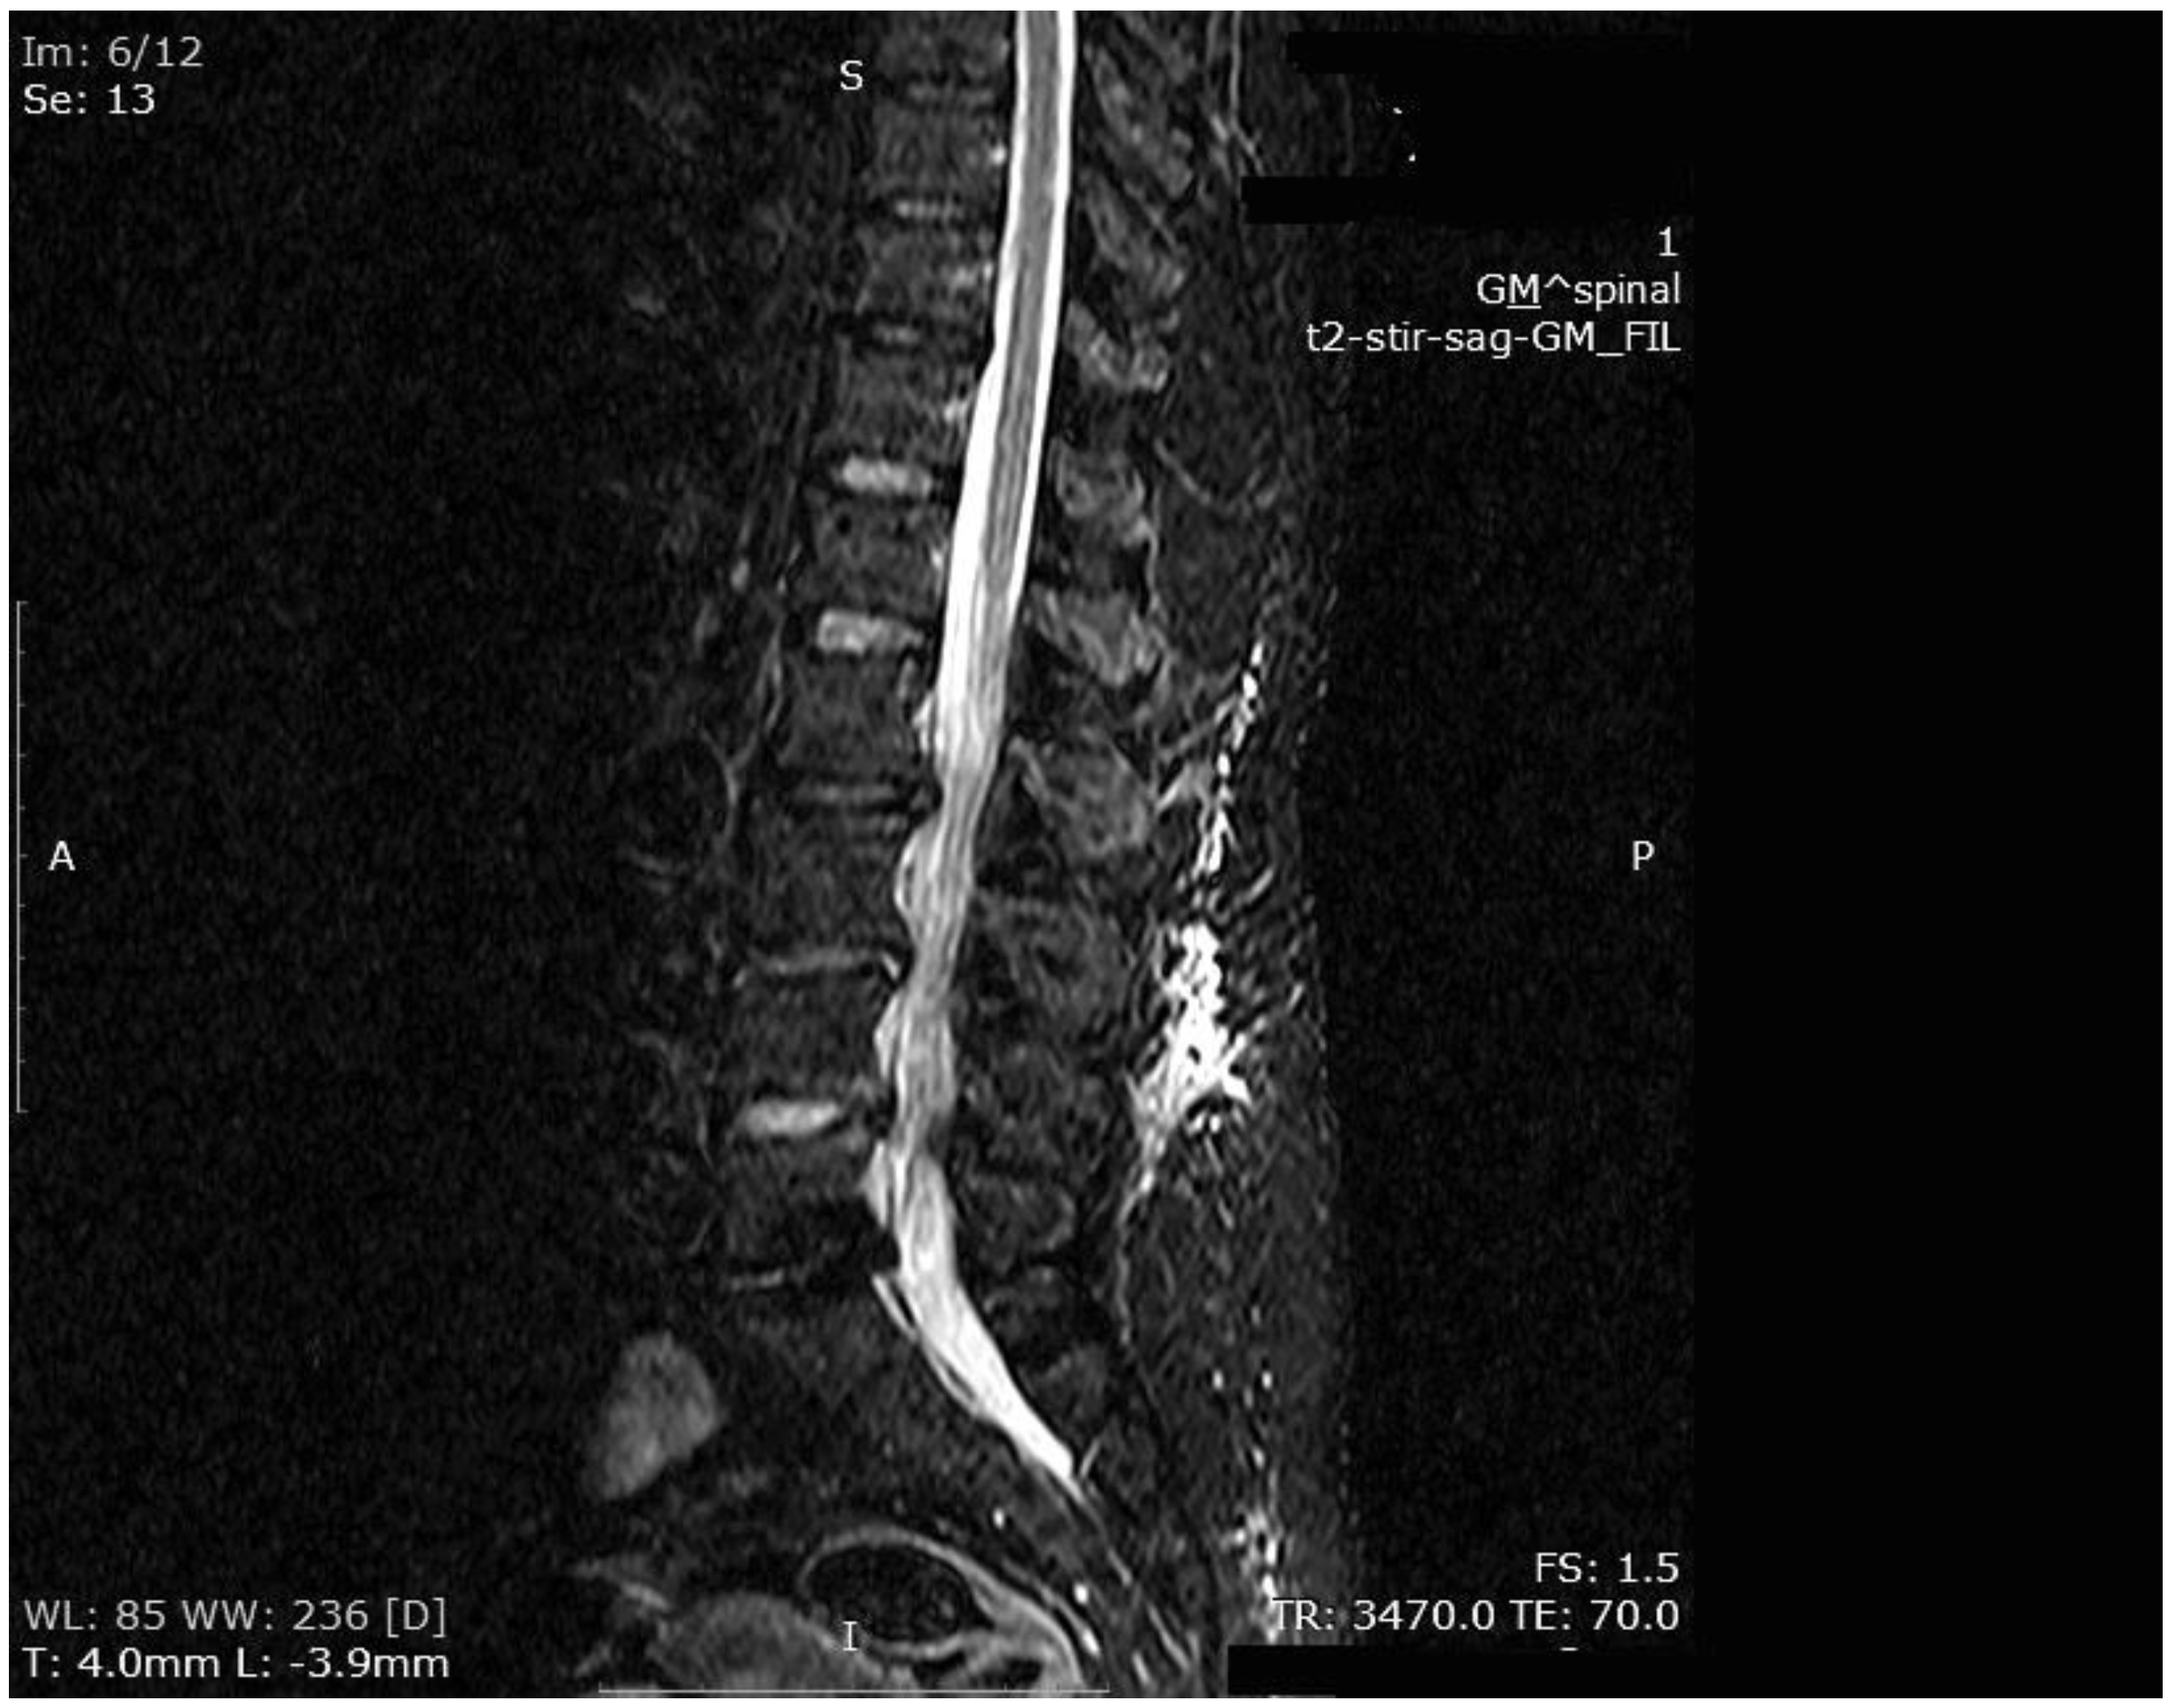

The mean number of total HBO2 sessions was 33 (±18.5) sessions. The HBO2 treatment was tolerated well by all patients except two. One patient had to receive analgesics (non-steroidal anti-inflammatories) before HBO2 sessions because she had severe back pain, and in one patient the treatment was interrupted for five days because of minor middle ear barotrauma. Improvements in clinical evaluations and laboratory findings were observed in all cases at the end of the HBO2 therapy. The mean erythrocyte sedimentation rate (ESR) value reduced from 76.1 (range, 6–129) to 45.7 (range, 5–81) mm/h, and the mean C-reactive protein (CRP) concentration reduced from 82.9 (range, 14–202) to 17.5 (range, 1–49.5) mg/L (normal limits; ESR: <20 mm/h, CRP: 0–5 mg/L). Infection resolution was adequately achieved in 12 of 13 patients on MR imaging at the end of HBO2 treatment or during the first month of follow-up (Figure 3, Figure 4 and Figure 5). There was no significant improvement in one patient. To extend the total clinical follow-up period up to three years (mean: 11 months; range, 1 month–3 years), telephone interviews were conducted to determine any recurrence of symptomatic clinical infection. No recurrence of infection, spinal instability, or deformity was seen in any patients.

Figure 3. MR imaging T1-weighted scan showing inflammatory infiltrates in the course of pre-HBO2 treatment.

Figure 4. MR imaging T2-weighted scan showing inflammatory infiltrates in the course of pre-HBO2 treatment.

Figure 5. MR imaging scan showing inflammatory infiltrates at the end of HBO2 treatment.